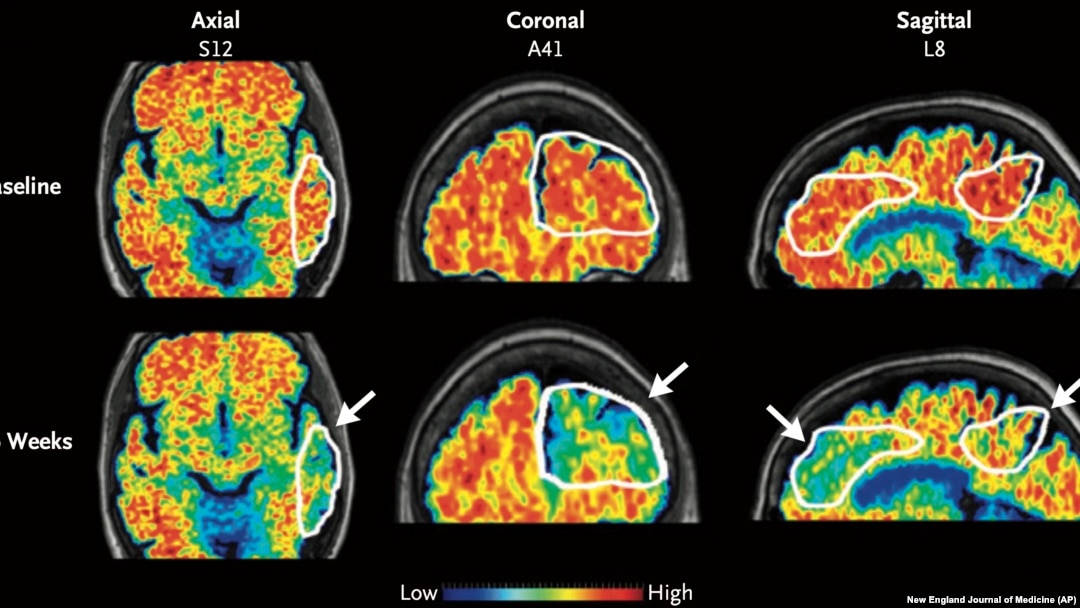

These PET scan images provided by the New England Journal of Medicine in January 2024 show a reduction in amyloid-beta levels in an Alzheimer's patient after focused ultrasound treatment to open the blood-brain barrier. (New England Journal of Medicine via AP)

PET scans show patients' amyloid levels before and after the six months of medication. There was about 32% greater plaque reduction in spots where the blood-brain barrier was breached compared to the same region on the brain's opposite side, researchers reported in the New England Journal of Medicine.